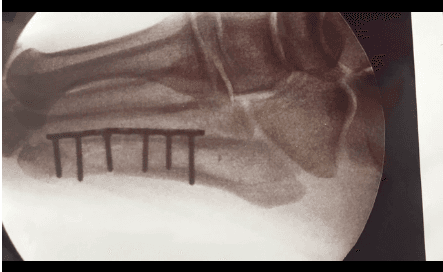

¡Hoy se ve así! El cantante ha engordado muchísimo de un tiempo para acá y justo en el arranque de las pocas fechas que darán, él se rompió un dedo del pie, por lo que tuvo que salir a escena con un yeso (negro muy rocker) y estuvo en una silla de ruedas ... de "metal".

Ouch! El artista tuvo que ser intervenido debido a la fractura en el pie izquierdo.

En un video que compartieron en sus redes sociales, la doctora que lo intervino explicó de qué se trata la lesión.